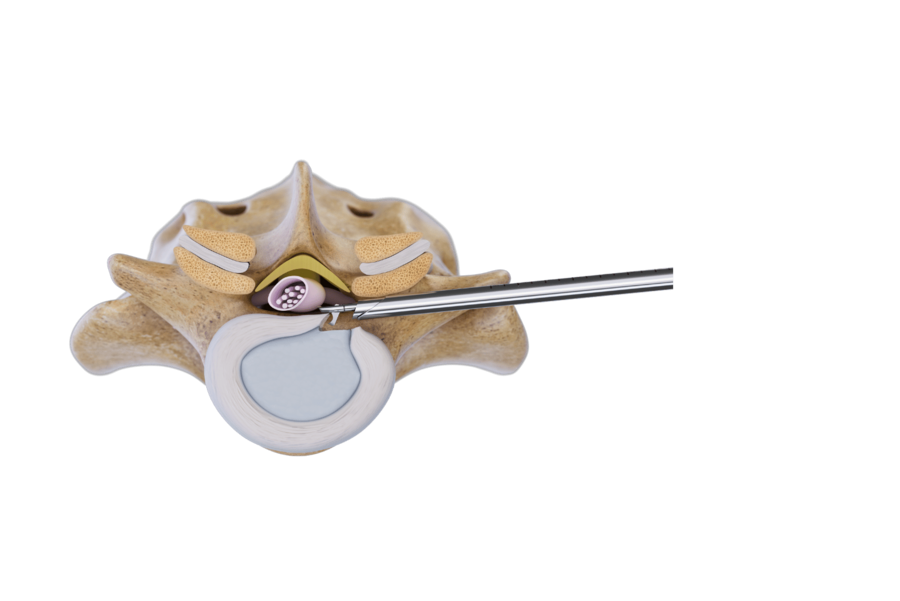

Foraminal technique

Foraminal approaches are minimally invasive techniques for treating spinal pathologies, located extra- and intraforaminally as well as inside the spinal canal and disc. It offers direct decompression with minimal surgical trauma. Depending on pathology, different access angles are used:

- Lateral Intra- and transforaminal approach for treating pathologies, located inside the intervertebral foramen and/ or inside the spinal canal: Angled at ~20°

- Posterolateral transforaminal approach”: Angled at ~45°, ideal for central disc pathologies. Narrow intervertebral foramina may require bone removal using manual or motorized burrs to ensure access.

- Extraforaminal approach for treating extraforaminal disc herniations and foraminal stenosis in lumbar and thoracic spine segments.

Using a lateral-to-posterolateral access angle (20°–30°), the puncture cannula is anchored in the caudal pedicle. The VERTEBRIS diskoscope and instruments are advanced cranially under full-endoscopic visualization to remove the herniated disc safely.